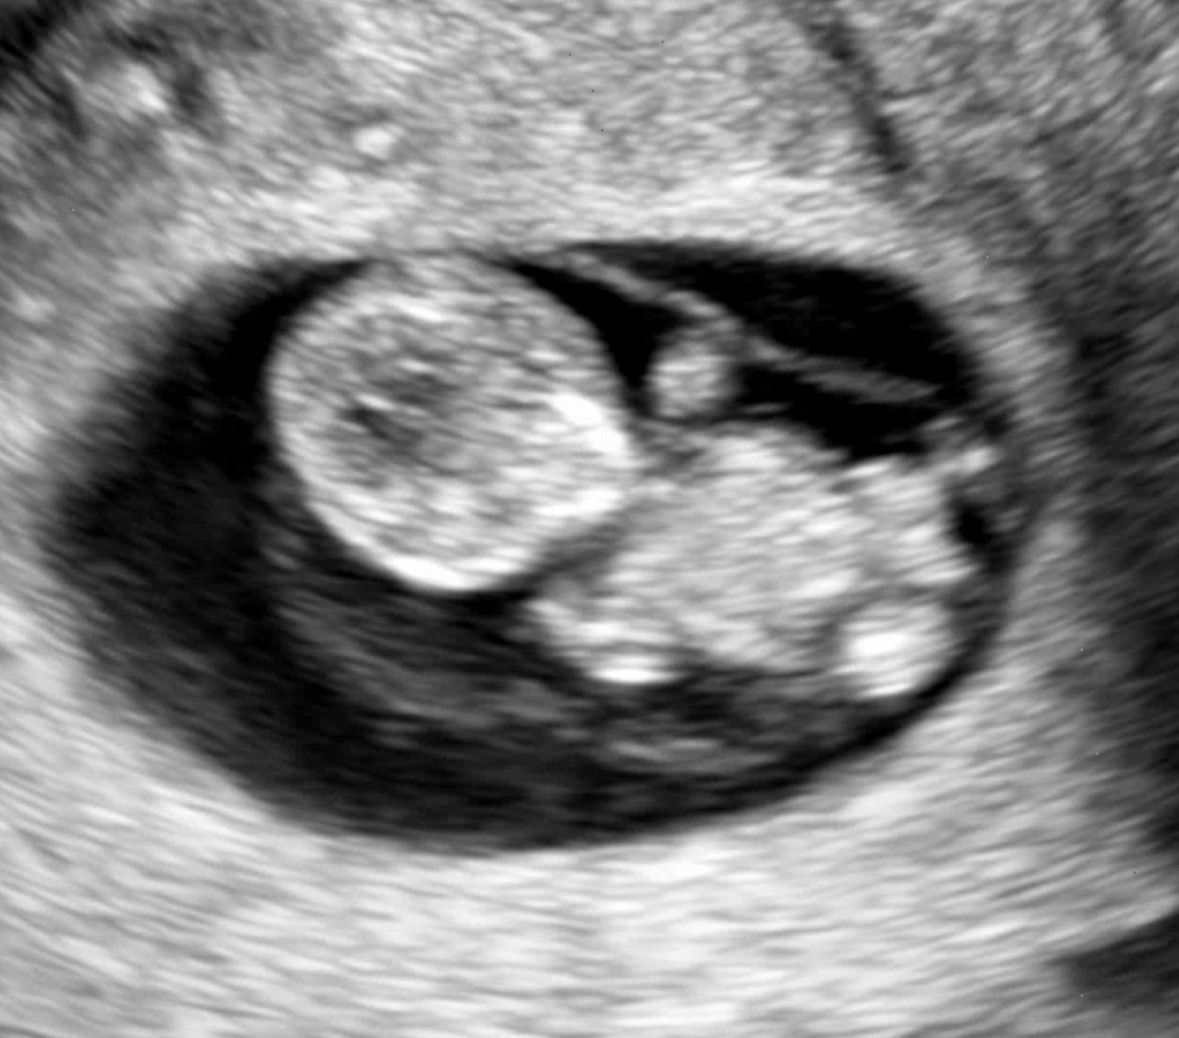

| 가슴 떨리는 임신 이야기를 공유해 주세요. | 결혼 후 자연임신을 시도했지만 계획처럼 이루어지지 않았고, 시험관을 권유받았음에도 일 때문에 2년 동안 과배란 유도만 진행했습니다. 이후 올해 인공수정 1차와 동결 시험관 1차를 시도하게 되었고, 신기하게도 배아이식 날짜가 생일과 겹쳤습니다. 그리고 선물처럼 임신에 성공하게 되었습니다. |